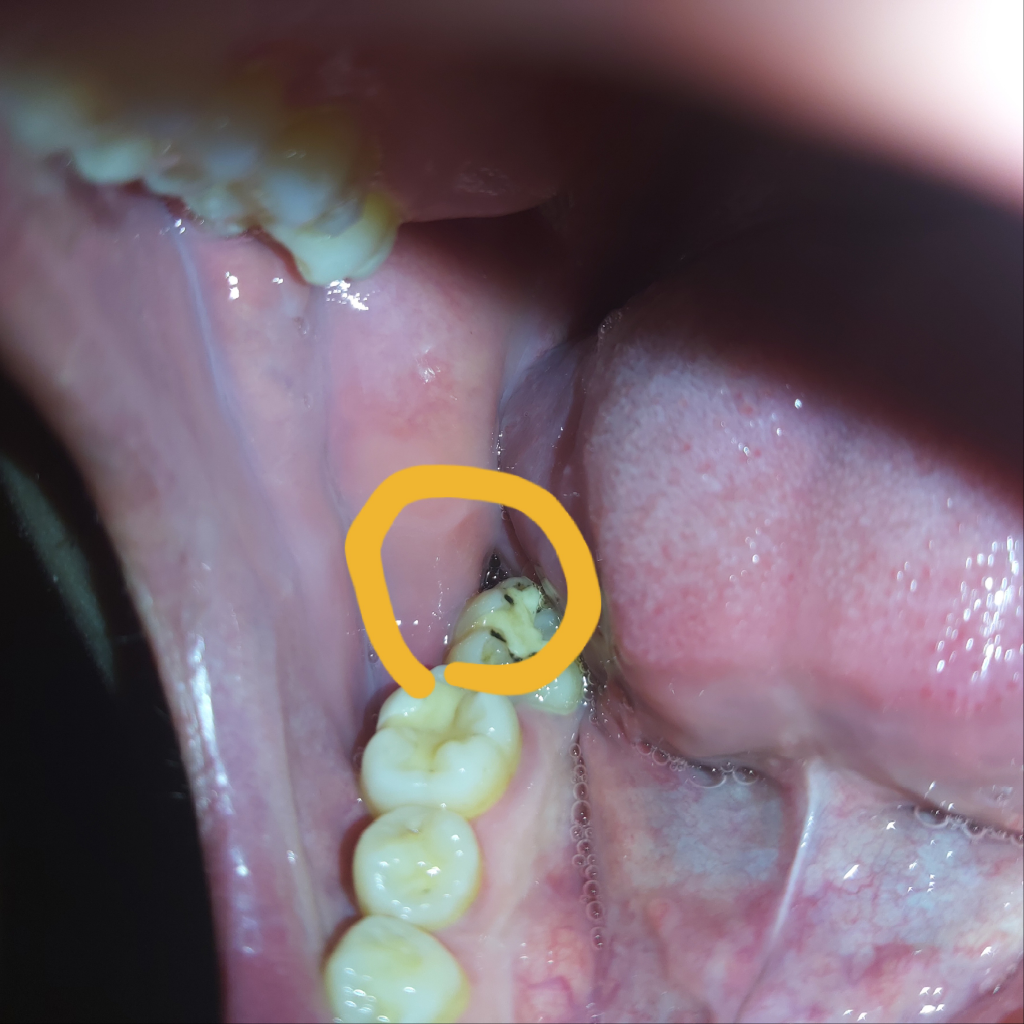

매복사랑니 발치 약 2주차인데 잘 치유되고 있는건지요?

매복사랑니 발치 후 약 2주가 되가는 중인데 음식물이 좀 끼어 주사기로 제거를 했습니다. 그런데 약간 피가 나고 하얀 부분 또한 보여 혹여 염증이 생기지는 않을까 걱정되어 질문드립니다.

하얀부분은 상피세포가 생겨나고 있을 수 있으며 극심한 통증이나 악취가 없다면 걱정안하셔도 됩니다.

사진으로 봐쓸 경우에는 잇몸이 아직 덜 차오른것으로 보입니다

사진상으로 보면 크게 문제가 잇어 보이진 않습니다. 사랑니 발치한곳이 완전히 아물려면 최소 한두달은 걸리니 그때까지는 음식물이 끼지 않도록 관리를 해주시는게 좋습니다.

2주 정도면 잘 아물고 있습니다. 발치한 구멍은 몇달이 지나야 다 차 올라옵니다. 음식물이 조금 끼더라도 그냥두면 밑에서 점점 차 올라옵니다. 아직 2주 밖에 안되었으니 건드리면 피가 나고 하지면 별다른 문제되지 않습니다.

사진 상으로 특별한 문제가 보이지는 않으며